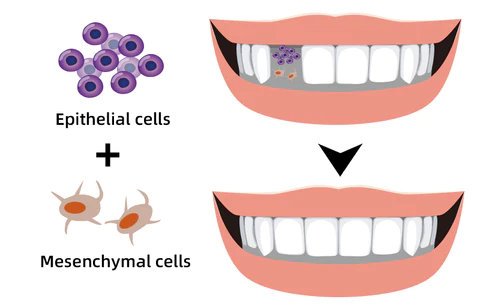

Stimulate The Regrowth Of Lost Teeth

FURZERO™ Herbal Brightening Oral Repair Foam can stimulate the gum bone to produce epithelial cells and mesenchymal cells, which will form new tooth germs and grow new teeth. It is a perfect solution for accidental tooth loss, tooth loss due to necrosis, and elderly tooth loss. No need to go to the dentist for expensive dentures.